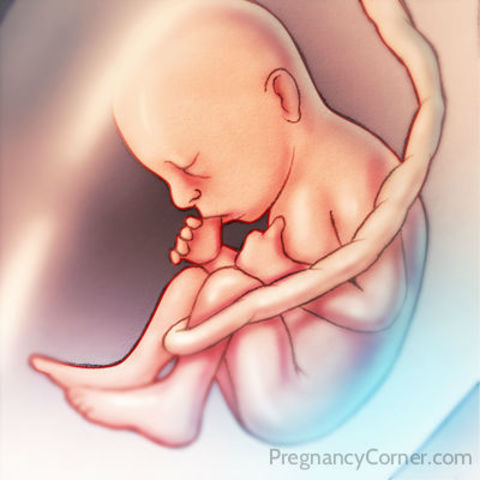

• Week Twelve Developments

Week Twelve Developments

The babay's vocal chords have fully developed. In addition, the baby's brain is fully formed and is able to recognize pain, the kidneys have also formed.

• Week Thirteen Developments

Week Thirteen Developments

In this stage the fetus is around 25 grams and about 8 cm long. The baby cartilage is beginning to be replaced by bone, and the chin and nosed are becoming well defined.

• Week Fourteen Developments

Week Fourteen Developments

The fetus is about 45 grams at this time and 9 cm long. Due to the hormones, the boys begin to have a prostrate gland and for the girls the ovaries are moving from the abdomen to the pelvis.